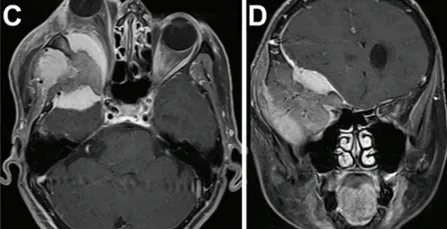

一名66岁女性患者因饮水困难及进行性神经功能恶化就诊,入院前数日内病情迅速加重。17年前,患者因右眼眼球突出于外院就诊,影像学检查诊断为蝶骨嵴外侧脑膜瘤;但因被告知病变无法手术,未接受治疗。此次就诊时,患者表现为重度眼球突出,眼球突出指数为2.41(图A)。术前照片显示右眼显著眼球突出。术前MRI和CT显示右侧巨大蝶骨嵴外侧脑膜瘤,伴有慢性钩回疝、脑干受压、中线移位1.4厘米及相关脑积水。术前右眼视力为20/400。患者还存在显著右侧偏瘫及嗜睡症状。

术前MRI(图C)显示显著眼球突出及视神经受压程度(眼球突出指数=2.41)。肿瘤在蝶骨眶区浸润的显著宽度(图D)。